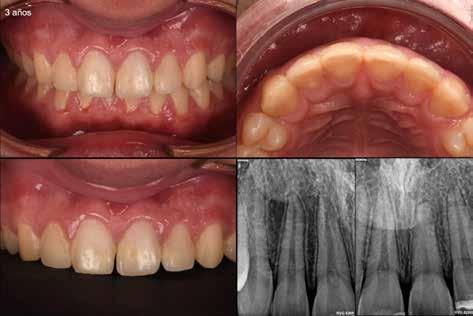

En el control a los tres años post-traumatismo (Figura 6), se observó obliteración parcial del conducto radicular del 2.1, con el paciente asintomático.

En este caso, el diente 2.1 presentaba una luxación lateral, y por el momento, aunque se está empezando a obliterar el conducto radicular, el tejido pulpar continua vital 3 años más tarde.

Figura 6: Fotografía clínica y radiografías de seguimiento de los 3 años post traumatismo.